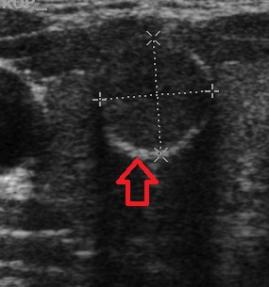

- Tiroid iltihabı (Hashimoto)

- Hashimato'da lazer tedavisi: İlaç dozlarının azaltılması veya kesilmesi ve kilo kontrolü !!!

- Hashimoto hastalığında destek tedavileri